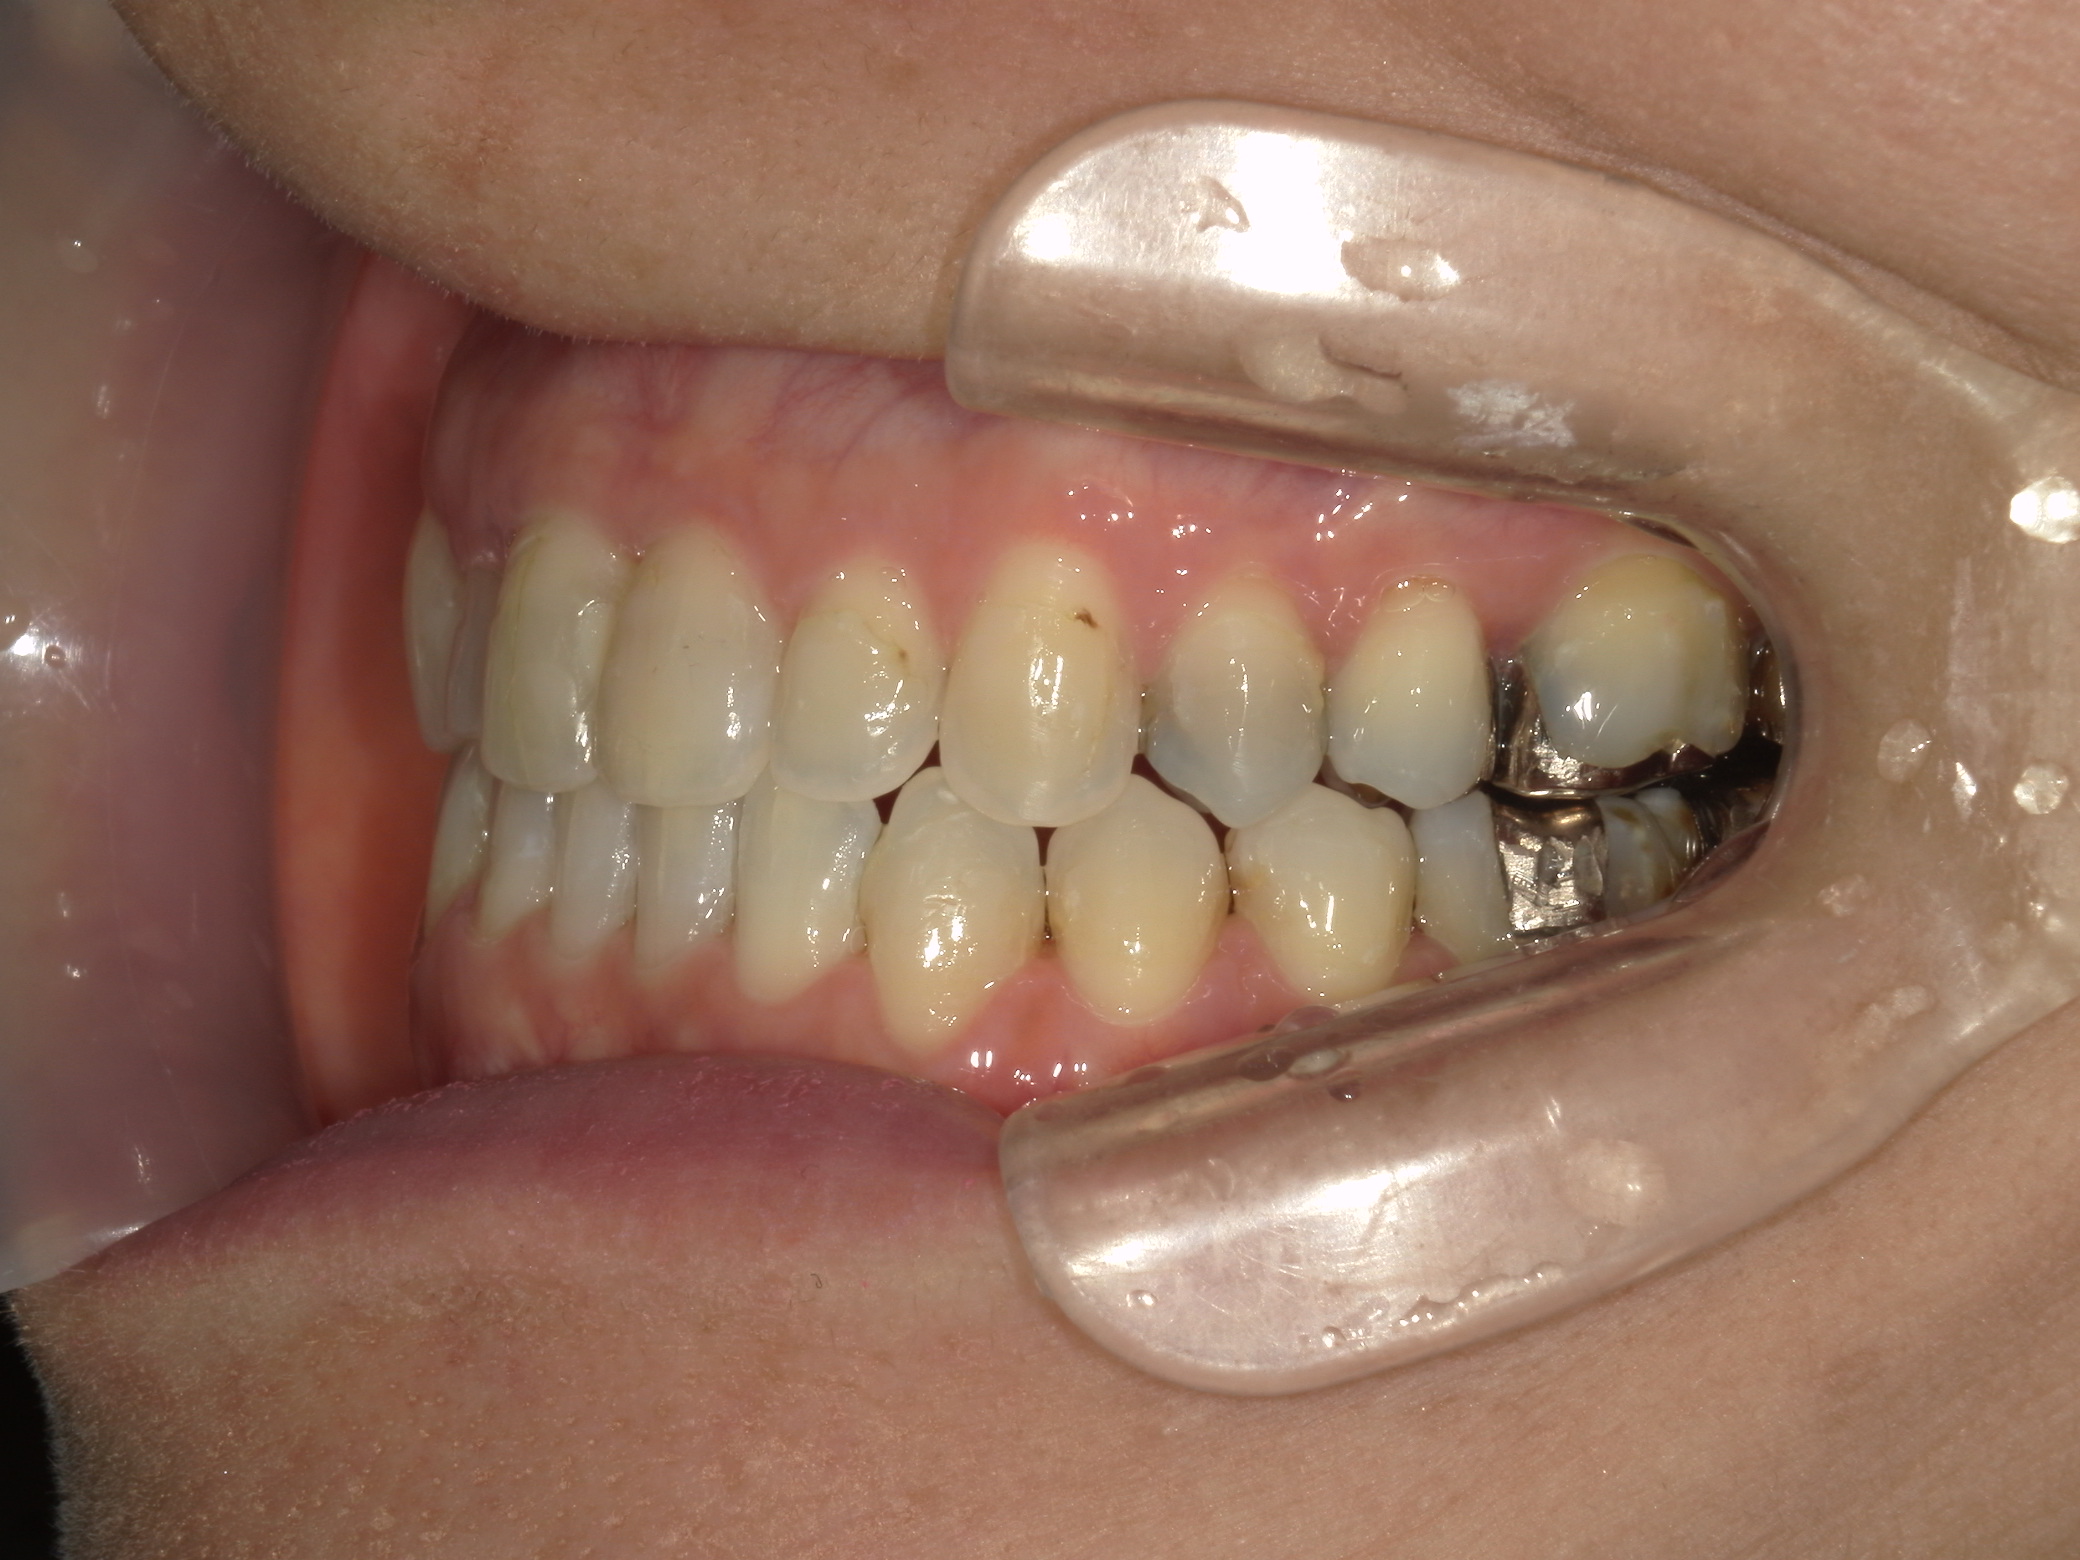

主訴: 受け口、歯並びが気になる。

右下第一小臼歯(1本)、右下親不知(1本)を抜歯。

右下第一大臼歯をセラミックへ変更。

③矯正装置を除去し、インビザライン矯正で歯列を整えました。